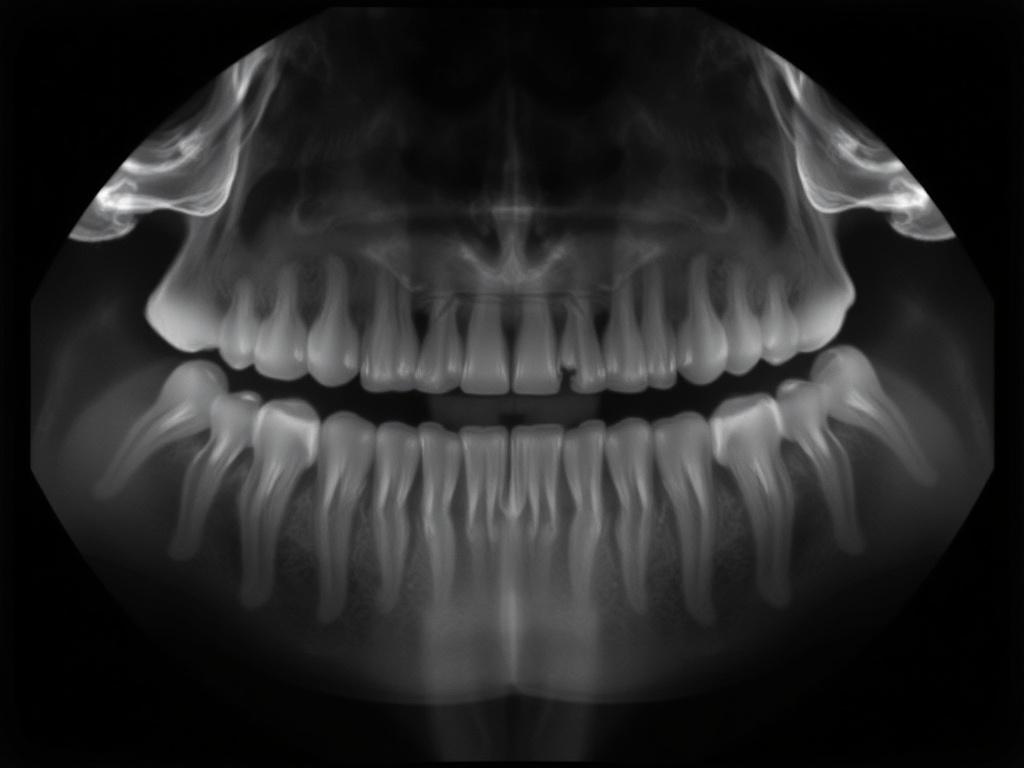

Прицельный снимок (periapical) показывает зуб полностью — от коронки до корневого конца и немного окружающих тканей. Его главное назначение — оценить корни, апикальную зону, периапикальные изменения и состояние периодонта. Этот снимок незаменим при подозрении на периодонтит, при планировании и контроле эндодонтического лечения, при травмах и при оценке реставраций около корня.

Важно понимать: прицельный снимок — это локальный инструмент. Он не предназначен для оценки всей челюсти или широкой зоны пародонта. Если нужна общая панорамная картина — используют панорамный снимок или прицельные снимки серии зубов в комбинации.